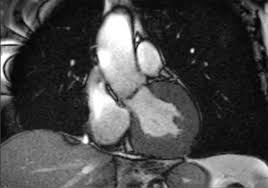

Die herzmuskelentzündung kann einen sehr unterschiedlichen verlauf nehmen. Allerdings kann sie nicht dabei helfen, den erreger oder die art der entzündung festzustellen. Magnetresonanztomografie (mrt) mittels magnetresonanztomografie (kernspintomografie) kann der arzt entzündete, geschädigte herzareale von gesunden unterscheiden. Ohne schnell einsetzende behandlung kommt es zu massiven störungen der herzfunktion bis hin zum sogenannten. Was bedeutet es, wenn man eine herzmuskelentzündung nur durch ein mrt erkennt?

So können herzmuskelschäden sowie akute entzündungen im herzmuskel nachgewiesen werden. Die besten anhaltspunkte für krankhafte vorgänge im herzmuskel liefert die kernspinuntersuchung. Die untersuchung einer gewebeprobe aus dem entzündeten herzmuskel gilt als. Ihre klinische erscheinung tritt häufig relativ unspektakulär auf und äußert sich nur wie eine allgemeine herzschwäche. Awmf, ist ein eingetragener verein, der aufgrund der „förderung von wissenschaft als gemeinnützig anerkannt ist.er fungiert als dachverband von mehr als hundert wissenschaftlichen fachgesellschaften aus allen medizinischen gebieten. Vorteile der magnetresonanztomographie des herzens. Sie wird im labor auf entzündungszellen und. Antwort auf diese frage gibt eine aktuelle studie. Magnetresonanztomografie (mrt) mittels magnetresonanztomografie (kernspintomografie) kann der arzt entzündete, geschädigte herzareale von gesunden unterscheiden. Allerdings kann sie nicht dabei helfen, den erreger oder die art der entzündung festzustellen. Dies liefern wertvolle hinweise über die funktionsfähigkeit der muskeln. Ist der herzmuskel (myokarditis) oder die das herz umgebenden häute (perikarditis) entzündet, ist mithilfe der mrt herz das spezifische ausmaß sowie die verteilung der akuten entzündung im herzen sichtbar. Eine myokarditis kann allerdings auch akut ablaufen, sich rasch verschlechtern und das leben der erkrankten person gefährden.

Typische veränderungen am herzmuskel zeigt eine kardiale magnetresonanztomografie (mrt).

Das bildgebende verfahren ermöglicht zudem die beurteilung des schweregrades der myokardialen entzündung und der begleitenden funktionsstörung sowie die objektivierung des verlaufes der erkrankung unter therapie, berichtet prof. Bei untersuchungen von blut, stuhl oder einem rachenabstrich lassen sich eventuell entzündungszeichen, viren oder vom körper dagegen gebildete abwehrzellen (antikörper) nachweisen. Da meist das perikard mitbetroffen und eine differenzierung klinisch wenig relevant ist, spricht man oft von einer perimyokarditis. Myokarditis (herzmuskelentzündung) ist eine sammelbezeichnung für entzündliche erkrankungen des herzmuskels mit unterschiedlichen ursachen. In seltenen fällen offenbart sich das krankheitsbild dramatisch, ähnlich einem. Patientinnen und patienten erhalten über eine vene eine kleine menge des kontrastmittels gadolinium. Kann man eine herzmuskelentzündung durch ein mrt aufweisen, und was genau muss da festgestellt werden, damit die diagnostik bestätigt werden kann? Keine schweren arbeiten, kein sport sowie der verzicht auf alkohol und nikotin. Im vordergrund steht hier die körperliche schonung. Im zuge dessen stechen die entzündungsherde hervor. Antwort auf diese frage gibt eine aktuelle studie. Mrt ermöglicht diagnose und verlaufskontrolle bei myokarditis nur die kombination mehrerer sequenzen bringt die erforderliche genauigkeit die myokarditis ist eine tückische erkrankung: Man findet örtlich im herzmuskel schwellungen, gewebszerstörungen oder vernarbungen.